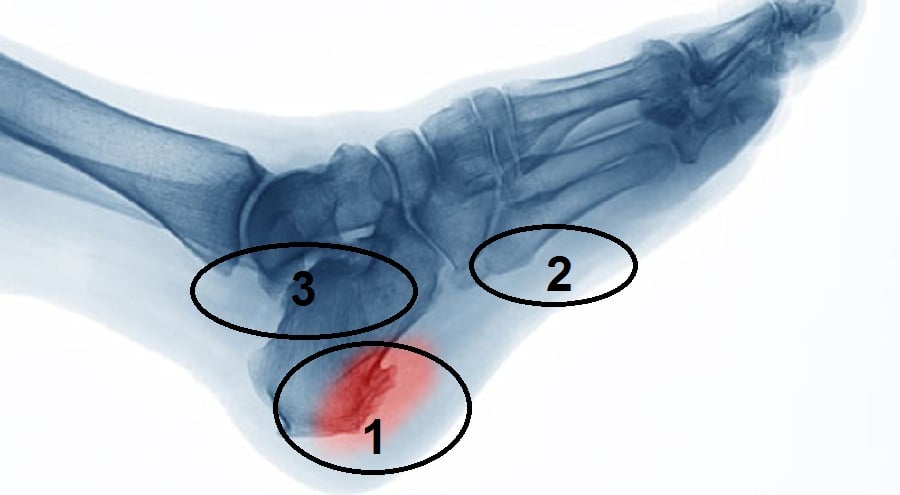

مسمار القدم او مسمار اخيليس مش هو سبب الم القدم الصبح وعدم المقدره على المشي الصبح.

من زمان علمونا غلط.. مناطق الالم الاشهر في الصوره من 1 -2- 3